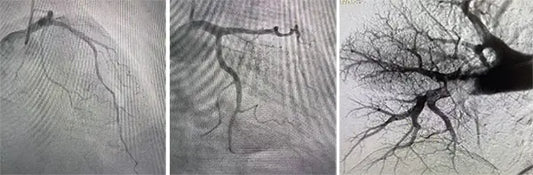

A team led by Dr. Liu Yuhao at Fuwai Central China Cardiovascular Hospital successfully performed an interventional closure of a 35mm Patent Ductus Arteriosus (PDA)—the largest diameter recorded globally. By...